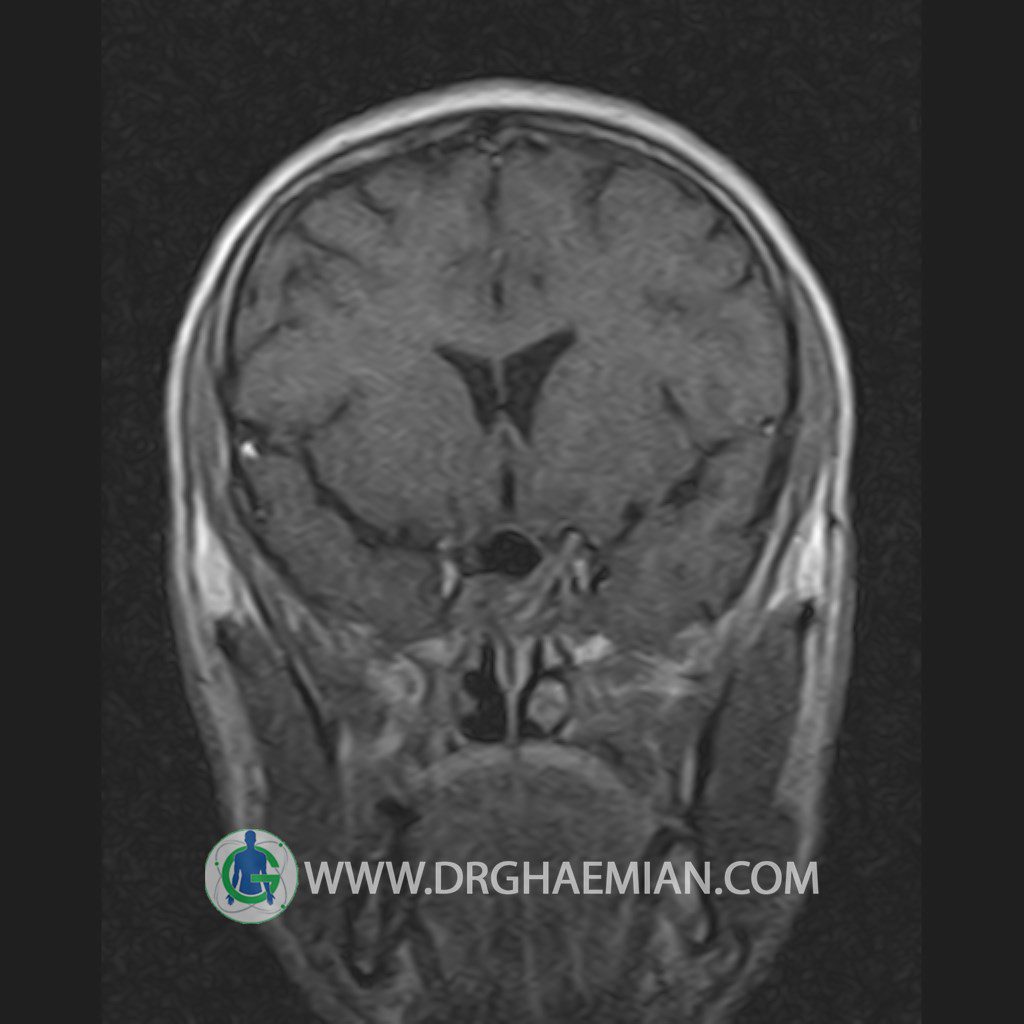

پزشکان اغلب از تصویربرداری ام آر آی برای تشخیص و درمان عارضه های پزشکی که فقط با استفاده از اشعه ایکس یا میدان مغناطیسی و امواج رادیویی قابل مشاهده است، استفاده می کنند. دستگاه ام آر آی تصاویر دقیق از ساختار های داخلی بدن ایجاد می کند. در این کیس یک میکروآدنوم در هیپوفیز بیمار مشاهده می شود.

HYPOPHYSIS MRI

(with and without contrast)

Technique: Axial , coronal T1 , Axial , coronal , sagittal T2 , Axial, coronal T1 post Gd & 64 dynamic thin coronal slices.

The infundibulum is centered and of normal size .

The optic chiasm and suprasellar spaces appear normal .

The cavernous sinus and imaged portions of the internal carotid artery and carotid siphon are unremarkable .

Evaluable portions of the neurocranium show no abnormalities .

The sphenoid sinus is clear and pneumatized .

Imaging of the hypothalamus after contrast medium administration was normal.

– Small hypoenhancing mass lesion ( 3 x 4 mm ) in posterior of pituitary stalk suggestive for micro adenoma

– Mucosal thickening in ethmoid & maxillary sinuses

is seen